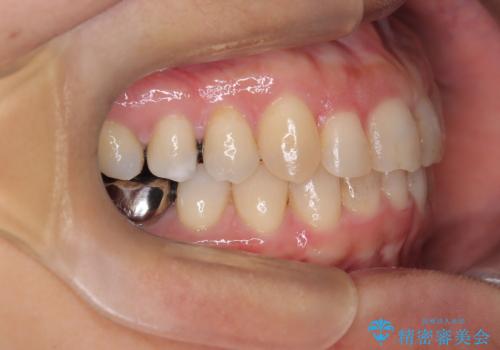

【インビザライン】重度叢生をなおしたい

- 全体的に歯並びをなおしたいことを主訴に来院されました。

上顎前歯が舌側傾斜していたため少し拡大を行いながら非抜歯で治療を行っています。

マウスピースをしっかり使用していただいたので、きれいな歯並びになりました。